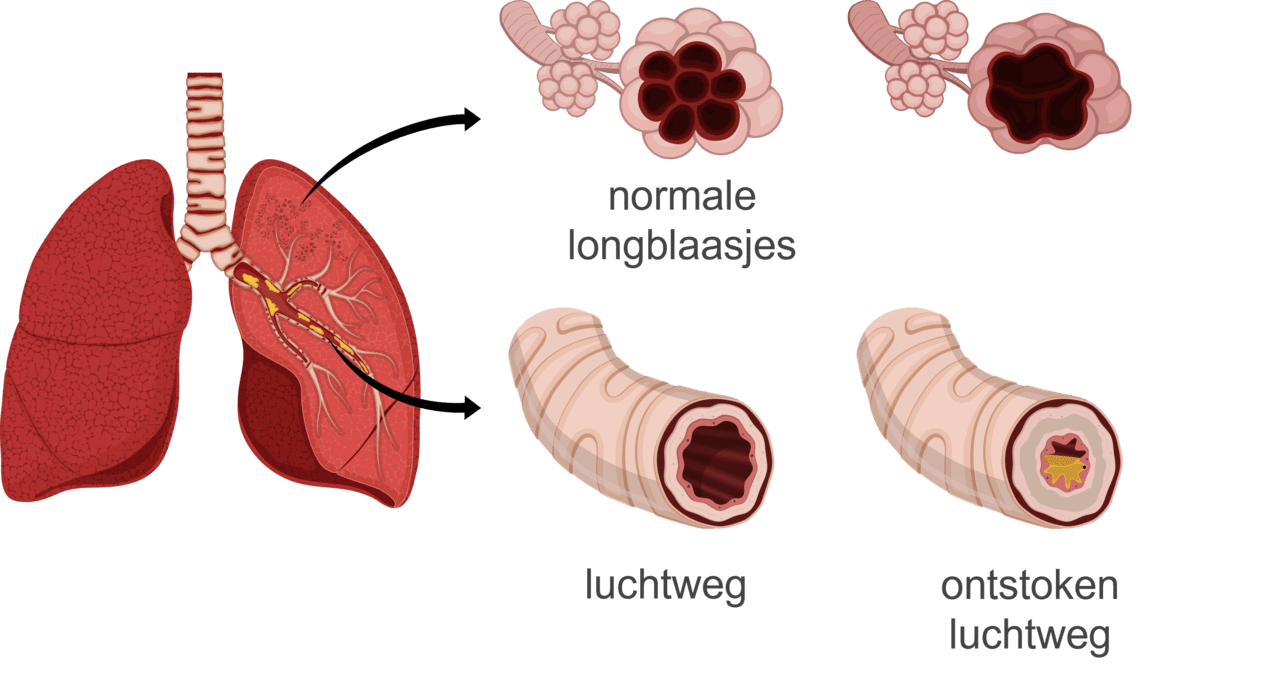

Astma is een chronische longziekte die niet overgaat. Symptomen van astma zijn benauwdheid, moeite met ademhalen en hoesten. Astma-aanvallen kunnen veroorzaakt worden door bepaalde stoffen die je inademt of flinke inspanning. Bij astma zijn de luchtwegen altijd ontstoken, wat leidt tot meer slijm en een dikker slijmvlies in de longen. Medicatie kan helpen om de luchtwegen weer open te zetten en het ademen te vergemakkelijken.

COPD is een chronische longziekte waarbij de longen altijd ontstoken zijn, wat leidt tot blijvende schade aan de longblaasjes. Deze schade is niet meer te genezen. De oorzaken van COPD kunnen onder andere een erfelijke ziekte zijn, maar vooral ontstaan door roken.